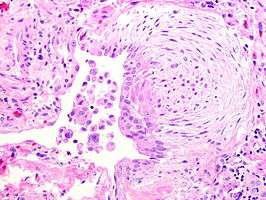

UIP may be diagnosed by a radiologist using computed tomography (CT) scan of the chest, or by a pathologist using tissue obtained by a lung biopsy. Radiologically, the main feature required for a confident diagnosis of UIP is honeycomb change in the periphery and the lower portions (bases) of the lungs.[2] The histologic hallmarks of UIP, as seen in lung tissue under a microscope by a pathologist, are interstitial fibrosis in a "patchwork pattern", honeycomb change and fibroblast foci (see images below).[3]